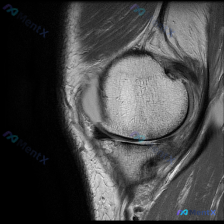

最近看到一个读片问题:给出了一张膝关节MRI冠状位T1加权像,怀疑存在软骨异常,要分析可能的观察结果。我整理了完整的分析思路,分享给大家。 一、影像基本情况 这是一张清晰的膝关节MRI冠状位T1加权像,切面位于关节中后部,可以看到股骨远端内侧髁、胫骨近端内侧平台、内侧半月板体部以及内侧副韧带结构,图...

整理了一个挺有代表性的读片病例,顺便把整个分析思路捋出来和大家讨论一下。 病例基础信息 这是一张膝关节轴位T1加权MRI图像,扫描层面位于髌股关节层面,图像对比度适中,解剖结构显示清晰,满足基础观察需求。 影像系统性观察结果 1. 骨骼结构:髌骨、股骨内外髁形态正常,骨皮质连续完整,骨髓信号均匀,未...

看到一张很有意思的读片病例,整理出来和大家分享,这个病例太能体现诊断思维的重要性了。 病例基本情况 用户提问:What diagnosis does the picture indicate?Chondral abnormality 提供的是一张膝关节MRI矢状位T2(或质子密度)加权图像,图像质量...